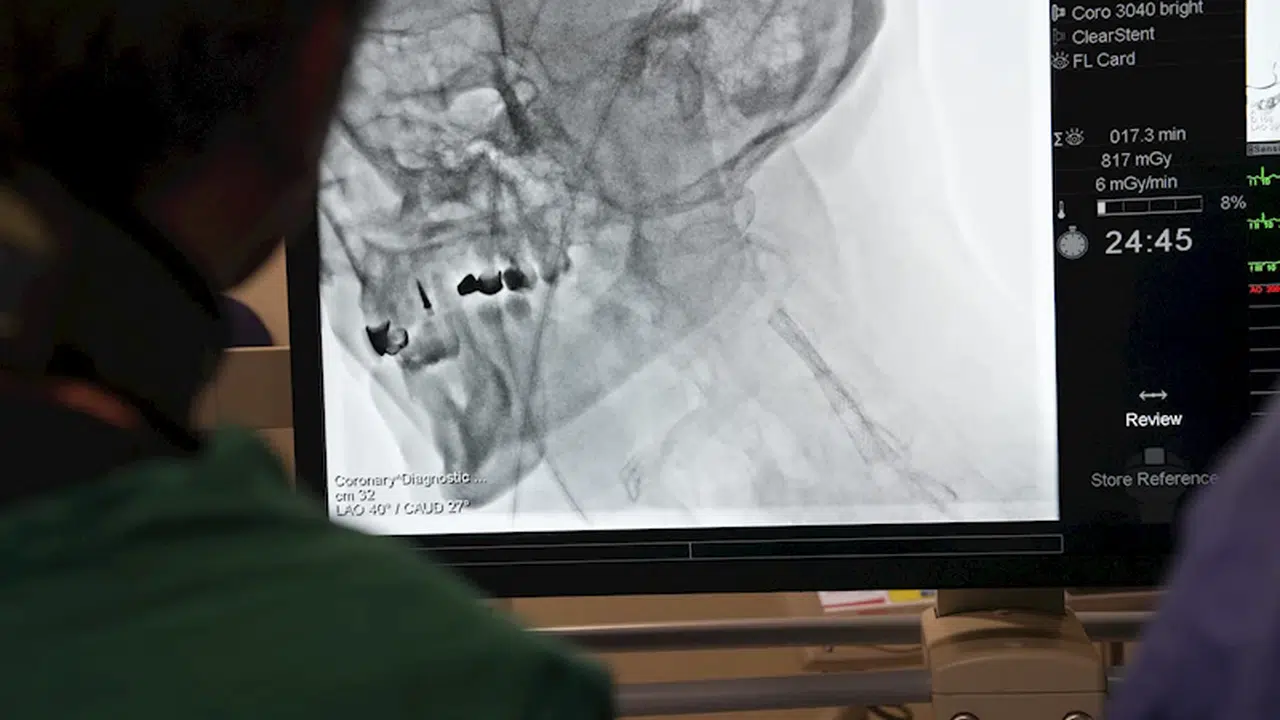

Tuğçe ODABAŞI-Fırat ALKIZ/İSTANBUL,(DHA)- Kardiyoloji uzmanları, yurt dışından gelen doktorlara yönelik ‘İleri Stent Teknikleri’ ve ‘Kronik Damar Açma’ alanlarında eğitim verdi. Prof. Dr. Ertuğrul Okuyan öncülüğünde gerçekleşen eğitim sırasında teorik bilgilerin yanı sıra, canlı operasyonlarla betonlaşmış damarlar açıldı.

Medipol Sağlık Grubu’nun düzenlediği ve bugün başlayan program, Kardiyoloji Uzmanı Prof. Dr. Ertuğrul Okuyan liderliğinde gerçekleştiriliyor. Özellikle Mısır, Pakistan, Tunus ve Cezayir gibi ülkelerden gelen doktorlara modern tıp alanındaki yenilikler ve ileri teknikler aktarıldı. ‘İleri Stent Teknikleri’ ve ‘Kronik Damar Açma’ gibi uygulamalar tüm detaylarıyla paylaşılırken, katılımcılara hem teorik bilgiler hem de canlı operasyon deneyimleri sunuldu. Eğitimler yarın da devam edecek.

Prof. Dr. Ertuğrul Okuyan, bugün başlayan ve 2 gün sürecek olan eğitim programının içeriği ve uyguladıkları ‘İleri Stent Teknikleri’ konusunda da önemli bilgiler paylaştı. Prof. Dr. Okuyan, Türkiye’nin kardiyovasküler girişimlerde dünya standartlarını yakaladığını ve birçok şehirde hem kamu hem özel sektörde bu alanda ileri düzey merkezlere sahip olduğunu belirterek, “Ülkemiz, kardiyoloji ve kardiyovasküler alanında çok iyi bir düzeye ulaştı. Artık Amerika Birleşik Devletleri veya Avrupa’nın önde gelen ülkelerinde yapılan her türlü işlem, Türkiye’de de büyük başarıyla uygulanabiliyor. Hekimlerimiz çok yetenekli, deneyimli ve sahip olduğumuz teknolojik altyapı dünya standartlarında” dedi.

‘BETONLAŞMIŞ VE SERTLEŞMİŞ DAMARLARI AÇMAK MÜMKÜN’

Prof. Dr. Okuyan, geleneksel yöntemlerle açılması mümkün olmayan damar tıkanıklıklarının, ileri teknikler sayesinde başarıyla tedavi edilebildiğini de söyleyerek, “Eskiden, çatallanma veya dallanma noktalarındaki darlıklar ya da uzun süredir tıkalı, betonlaşmış, kireçlenmiş damarlar açılamıyordu. Ancak günümüzde kullandığımız ileri teknikler sayesinde bu sorunların üstesinden geliyoruz” diye konuştu.

“Bu tekniklerin temelinde, damar içi ultrason gibi görüntüleme yöntemleriyle damar morfolojisinin detaylı bir şekilde incelenmesi ve özel cihazların yardımıyla tıkanıklıkların açılması yer alıyor” diyen Prof. Dr. Okuyan, “Damar içi tıraşlama yöntemleri, taşırma kateterleri ve özel malzemelerle artık eskiden açamadığımız damarları açabiliyoruz. Bu işlemler, ileri stentleme teknikleri olarak adlandırılıyor” ifadelerini kullandı.